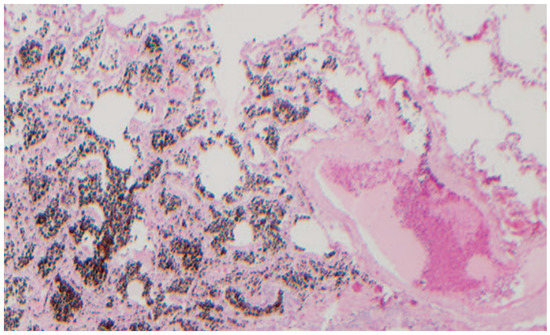

3.1.1. Case 1

3.1.2. Case 2